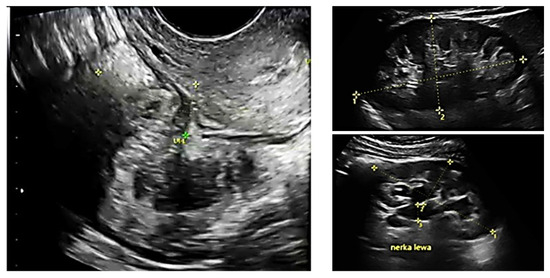

2.2. Ultrasound Examination

- Improves diagnostic efficiency as the surgeon performing the examination learns to analyze ultrasound images more effectively, which can be compared with images of endometrial changes during surgery. This correlation contributes to better assessment in subsequent examinations;

| R (Right Ureter) | R,L (Both Ureters) | L (Left Ureter) | |

|---|---|---|---|

| Surgery | 19 | 67 | 41 |

| Imaging | 17 | 23 | 25 |

| Imaging% | 89.47% | 34.33% | 60.98% |